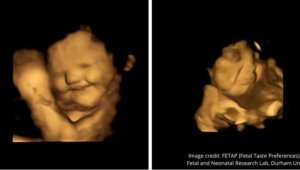

- 胎儿表情透露对味道喜好 笑脸反应因为这气味(图)